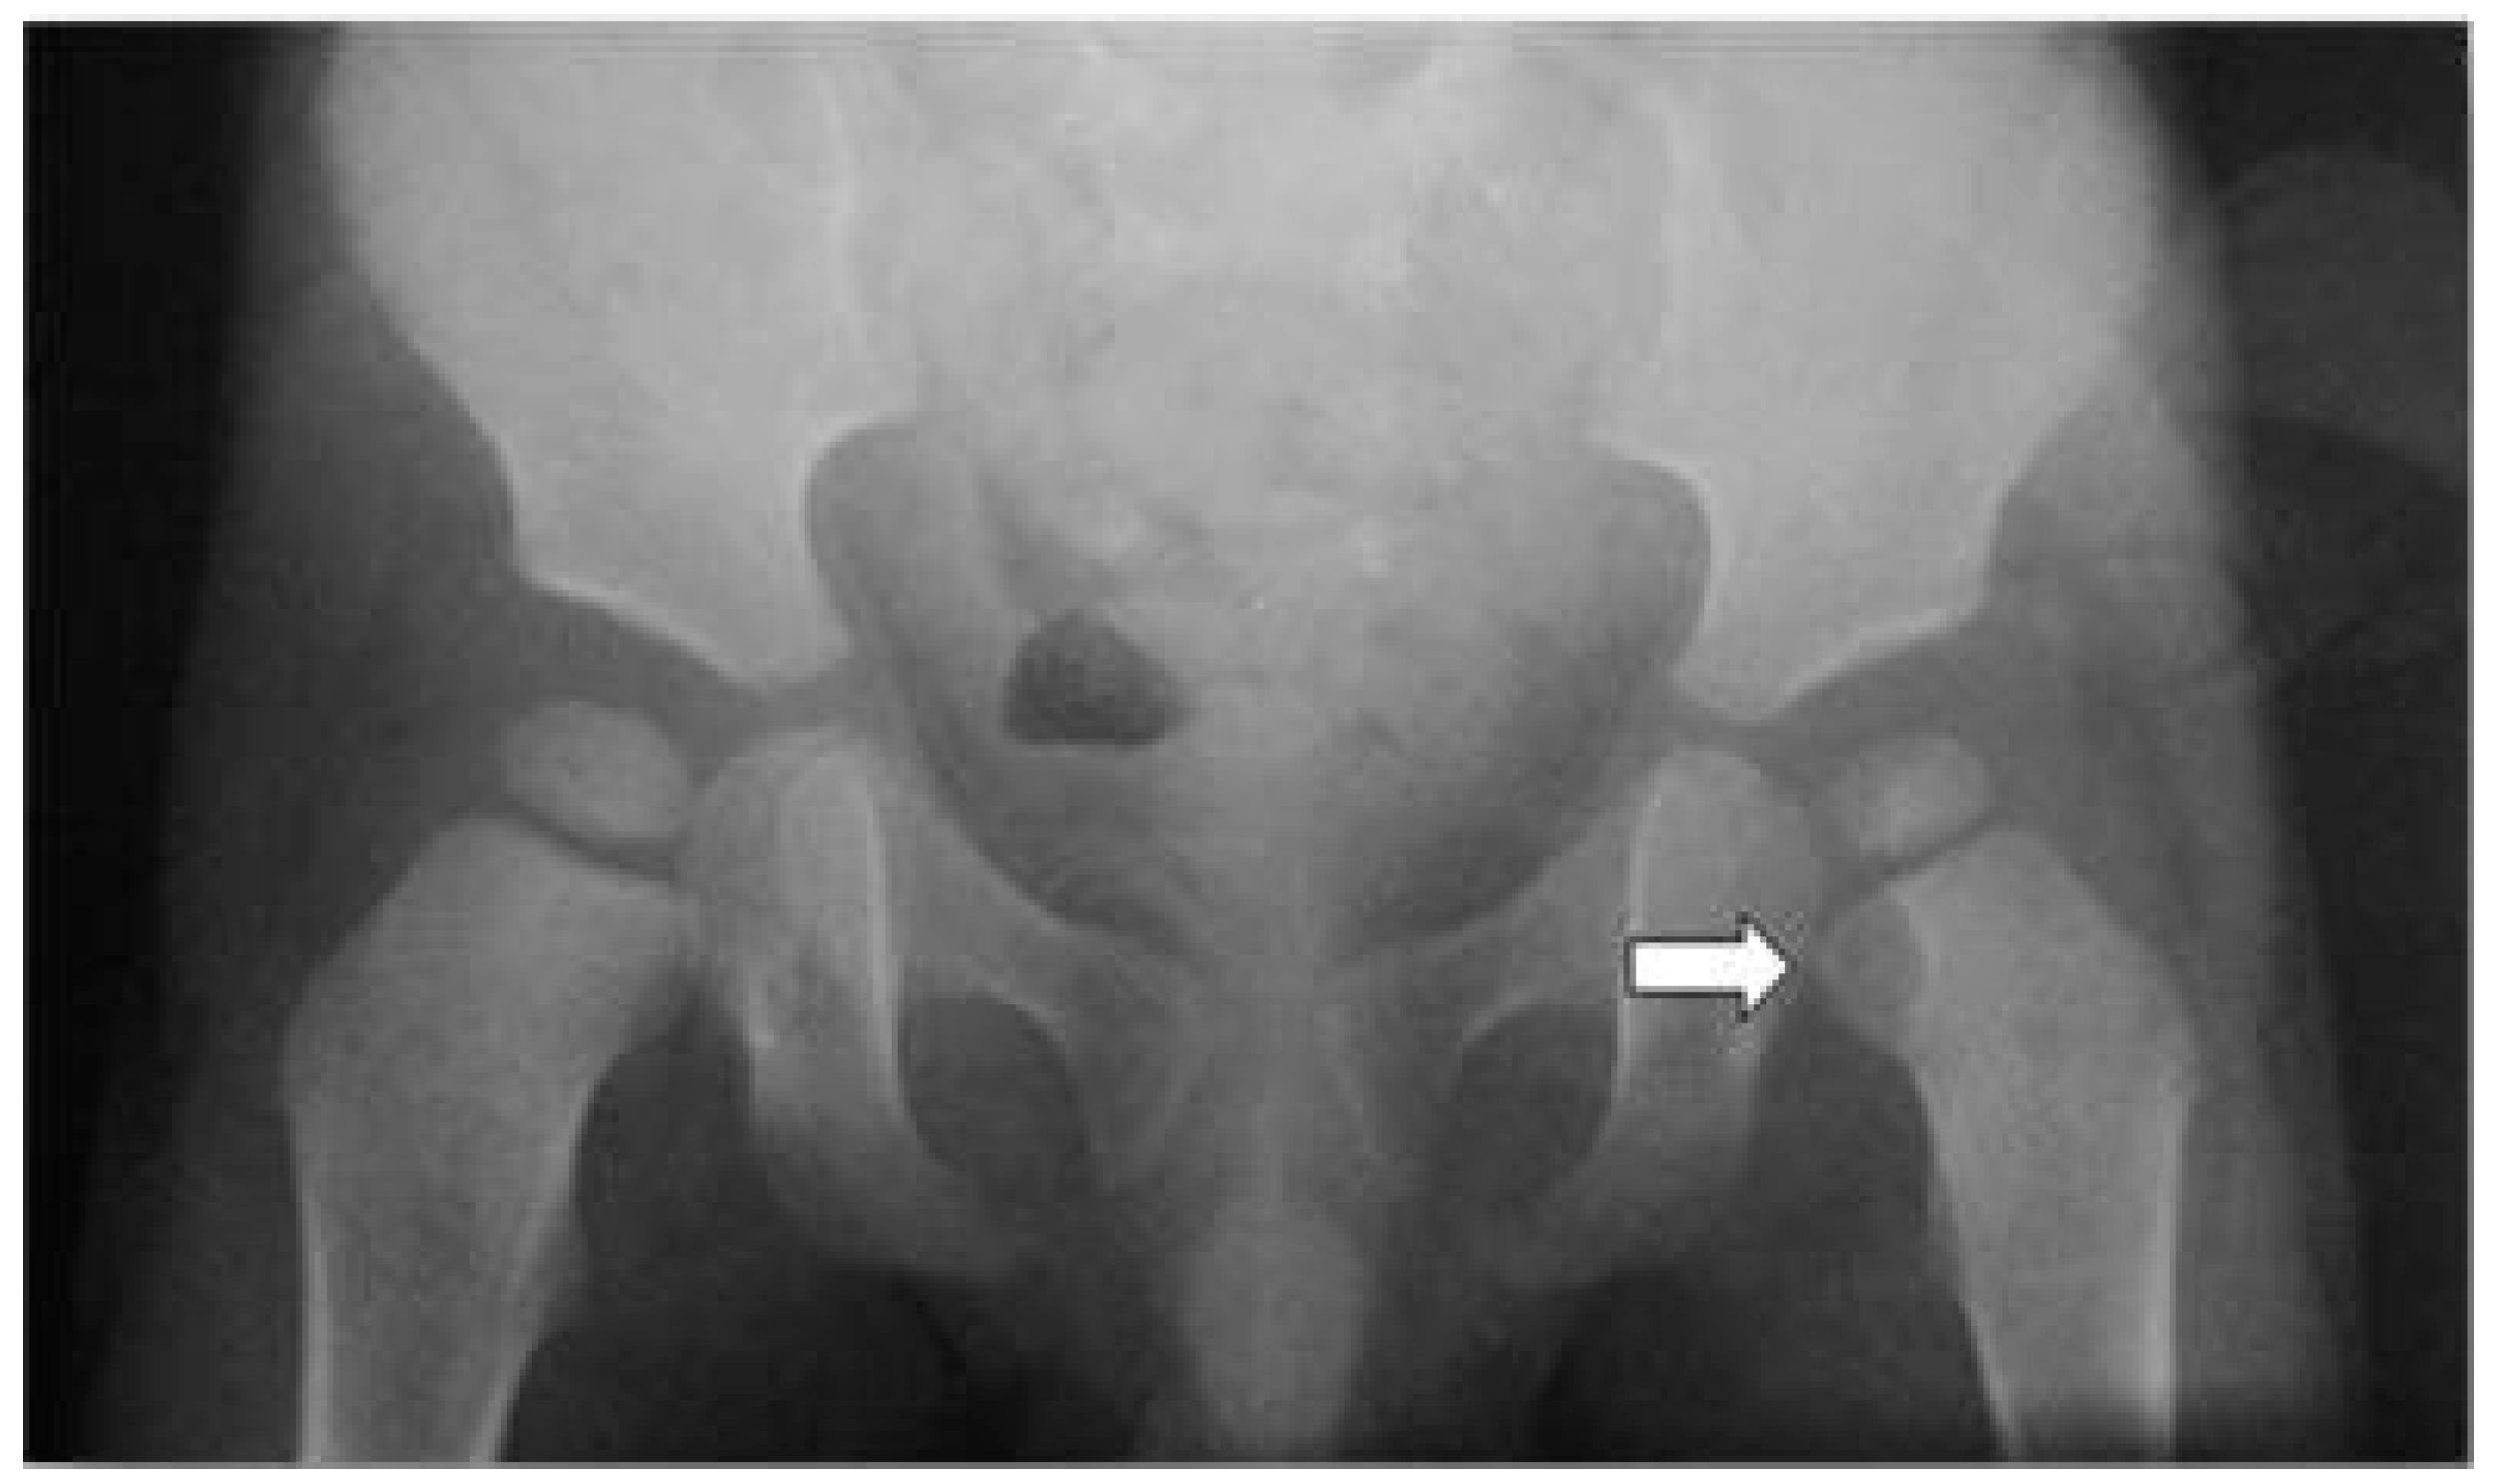

:1. Case Presentation